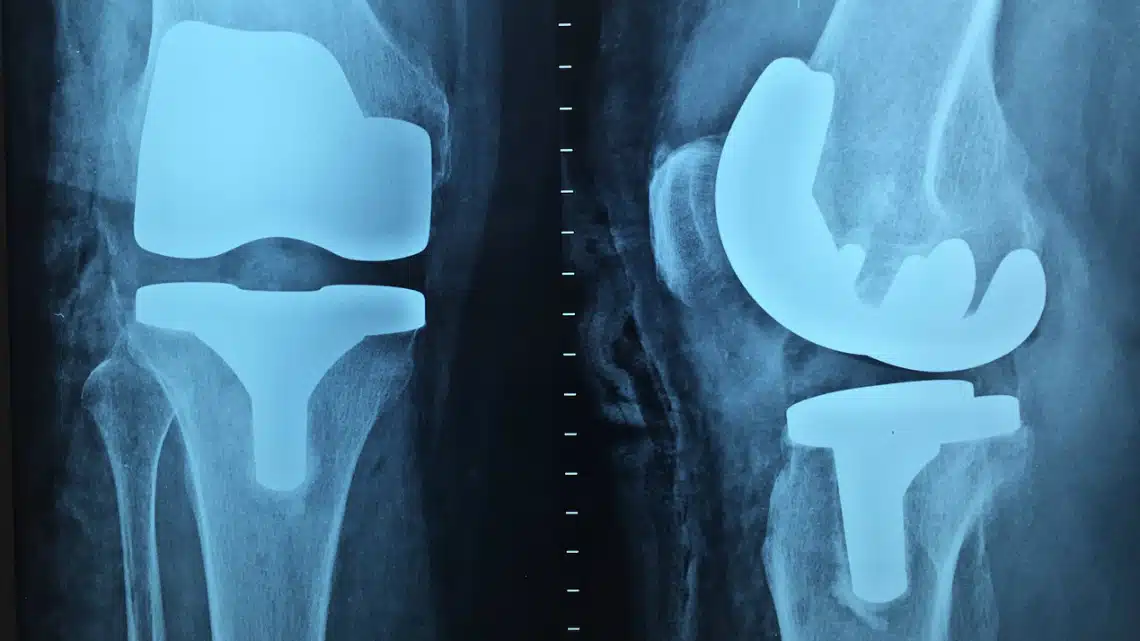

2. Стави – не е нужно да си спортист, за да изпитваш болка в ставите. Колагенът действа като масло върху ръждясал механизъм. Киселините в колагена имат и противовъзпалителни свойства, които ще облекчат сковаността ти.

6. Кости – колагенът храни клетки, които отговарят за костите и които се наричат остеобласти. Те помагат за предотвратяването на остеопорозата.

Тя засяга много възрастни и се получава неусетно. Остеопорозата прави костите ти по-податливи на фрактури и счупвания, дори при леки удари. Остеопорозата е причина и за костни и ставни болки. Ранните симптоми на остеопороза включват: лесно пукване или чупене на кости, болки и намаляване на ръста – сигурно си забелязал как възрастните хора се изгърбват и „смаляват“ и това е една от причините. Колагенът не е единственият начин да се справиш с трудното положение – има храни, които ще засилят ефекта на добавката.